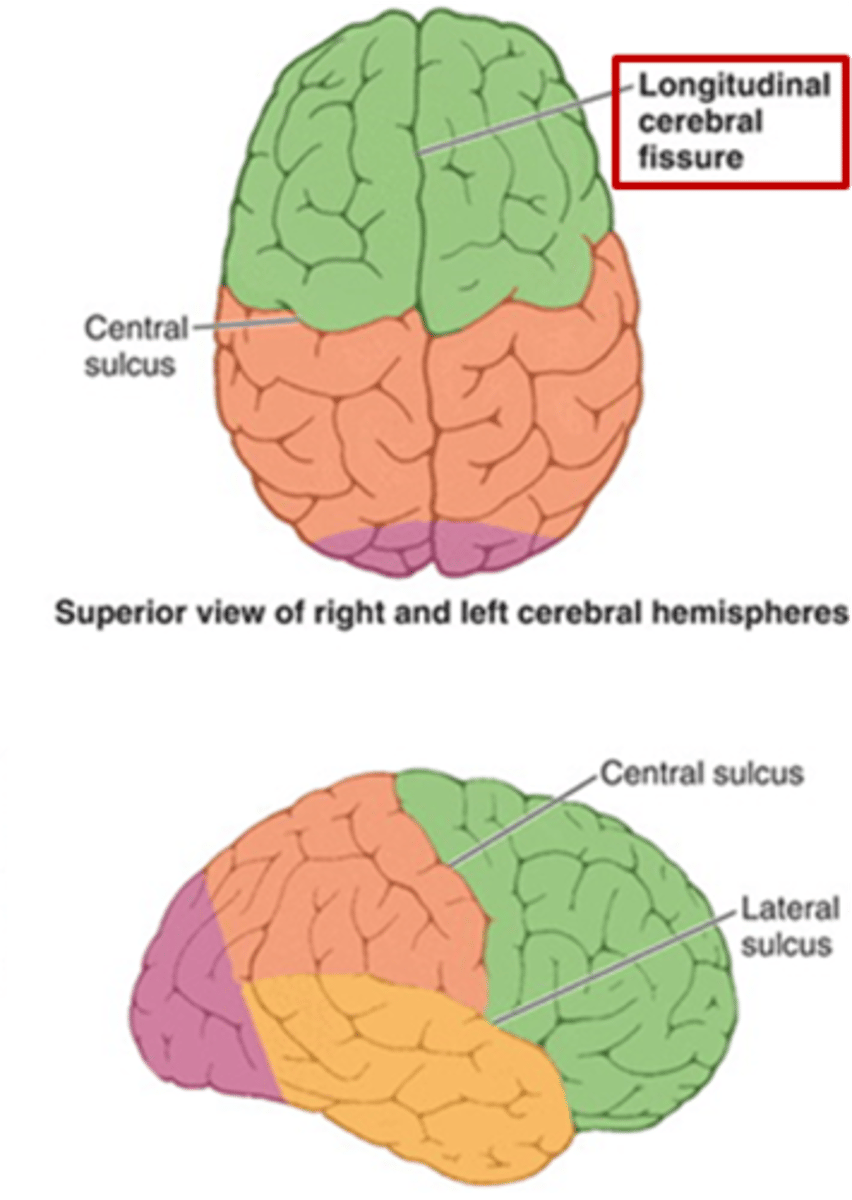

what are the 3 regions of the brain?

1. cerebrum (cerebral hemispheres)

2. brainstem

3. cerebellum

what are the 4 main lobes of the cerebrum?

FPOT

1. frontal

2. parietal

3. temporal

4. occipital

what lobe of the cerebrum is involved with motor and personality?

FPOT

frontal

what lobe of the cerebrum is involved with sensory?

FPOT

parietal

what lobe of the cerebrum is involved in hearing and memory?

FPOT

temporal

what lobe of the cerebrum is involved in vision?

FPOT

occipital

what additional lobe of the cerebrum is involved in receiving, processing, and integrating various types of information (taste, visceral sensation, pain, and balance)?

insula

additional lobe = insula and limbic lobe

what additional lobe of the cerebrum is involved in processing complex aspects of learning, memory, and emotion?

limbic lobe

additional lobe = insula and limbic lobe

which sulcus separates the cerebral hemispheres?

longitudinal fissure

which sulcus divides the frontal lobe from the parietal lobe and divides the precentral and postcentral gyrus?

central sulcus

which sulcus divides the parietal lobe from the temporal lobe?

lateral (sylvian) sulcus/fissure

which sulcus separates the parietal lobe from the occipital lobe?

parieto-occipital sulcus

which gyrus is the primary motor complex?

precentral gyrus

which gyrus is the primary somatosensory complex?

postcentral gyrus